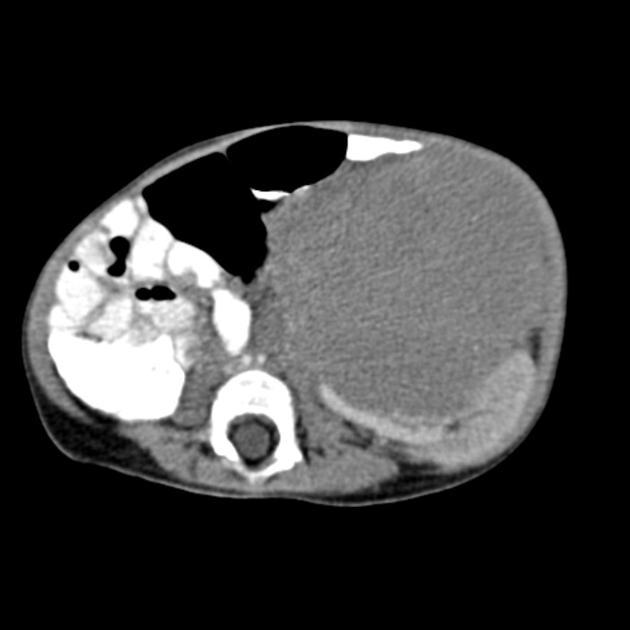

Main differences between Wilms and Neuroblastoma

Calcifications and metastasis to bones in neuroblastoma

Invasion of vessels and well defined in Wilms (neuro encases and is irreguar)

4 years in Wilms and 2 years in Neuro